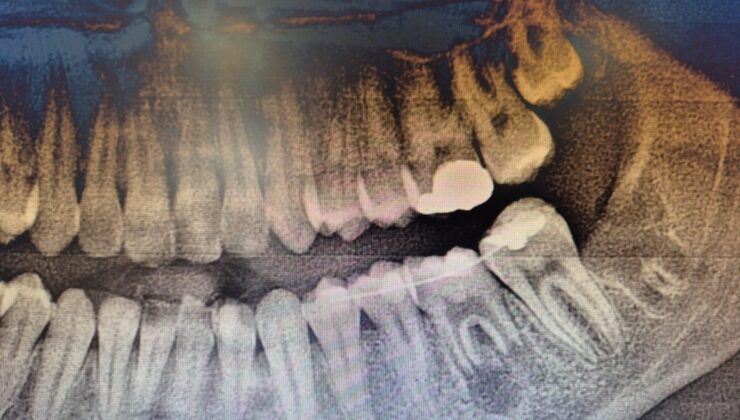

Karabük Ağız ve Diş Sağlığı Eğitim ve Araştırma Hastanesi’nde, 16 yaşındaki bir hastaya diş kaybına karşı doğal ve etkili bir çözüm olan “diş ototransplantasyonu” yöntemi başarıyla uygulandı.

Edinilen bilgilere göre; Genç hastanın ileri düzey çürük nedeniyle tedavi amaçlı olarak bir daimi azı dişi çekildi. Ancak çocuk yaşta çene gelişimi devam ettiği için implant uygulaması gibi klasik tedavi yöntemleri uygun görülmedi. Bu nedenle hastanın kendi ağzında kemik içinde gömülü halde bulunan üçüncü azı dişi (yirmi yaş dişi), uzman ekip tarafından operasyon mikroskobu eşliğinde cerrahi operasyonla çıkarıldı ve hazırlanan yuvaya nakledildi. Ayrıca, dişin daha sağlıklı bir şekilde iyileşebilmesi için çocuğun kendi kanından elde edilen PRF (kişinin kendi kanından elde edilen, hücre yenilenmesini destekleyen doğal bir biyomateryal) nakil işlemi öncesinde hazırlanan yuvaya konuldu.Bu özel işlem, hastanın kendi dişi kullanıldığı için hem doğal görünüm hem de fonksiyon açısından büyük avantaj sağlamaktadır. Dişin vücut tarafından kabul edilme ihtimali yüksek olduğu için uzun vadeli başarı oranları da oldukça yüksektir.

Hastanın tedavisi, Endodonti Anabilim Dalı öğretim üyesi Doç. Dr. Olcay Özdemir ile Ağız, Diş ve Çene Cerrahisi Anabilim Dalı öğretim üyesi Dr. Öğr. Üyesi Muhammed Abdullah Çege tarafından başarılı bir şekilde gerçekleştirilmiştir.

Uzmanlar, bu yöntemin özellikle çocuk ve genç hastalarda, uygun şartlar oluştuğunda, diş kayıplarında güvenilir bir alternatif olabileceğini vurguladı”dedi…